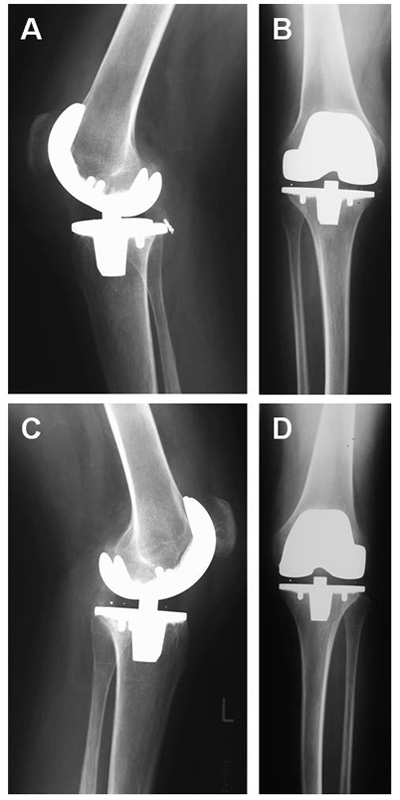

Figure 4

One year postoperative x-rays of both knees. Correct anatomic position of the prostheses, no signs of loosening. (a) Right knee lateral view (b) Right knee anterior-posterior view (c) Left knee lateral view (d) Left knee anterior-posterior view.

Thereafter the patient could be mobilised with crutches and left the hospital on day 26. One year after the operation the patient reached a bilateral flexion of 90° passively and up to 80° actively with a persistent extension deficit of 5°. He was able to walk continuously without assistance for up to three hours, and rising from a chair posed no further problem. X-rays showed no signs of loosening (fig. 4).